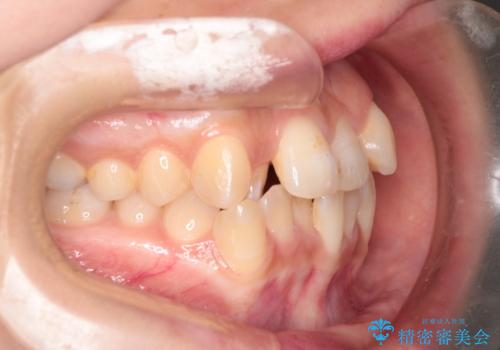

重度の歯並びの乱れを改善|上下4本抜歯と審美ワイヤー矯正で美しい歯列へ

- 患者様は、歯並びのガタガタ(重度の叢生)を改善したいとのことで来院されました。診察すると、歯列のスペース不足が著しく、前歯が重なり合い、噛み合わせにも影響が出ている状態でした。歯をきれいに並べるためには抜歯によるスペース確保が不可欠と判断し、上下の小臼歯4本を抜歯したうえで、目立ちにくい審美ワイヤー矯正(白いワイヤーと透明ブラケット)を用いた治療計画を立てました。

抜歯によって歯を動かすためのスペースを確保。その後、審美ワイヤー矯正を用いて歯を1本ずつ適切な位置に誘導しながら、噛み合わせのバランスも整えていきました。時間はかかりましたが、ガタガタの歯並びがきれいに整い、機能的にも審美的にも満足のいく仕上がりとなりました。患者様からは「歯並びが劇的に改善し、見た目だけでなく噛みやすさも向上した」と喜びの声をいただきました。